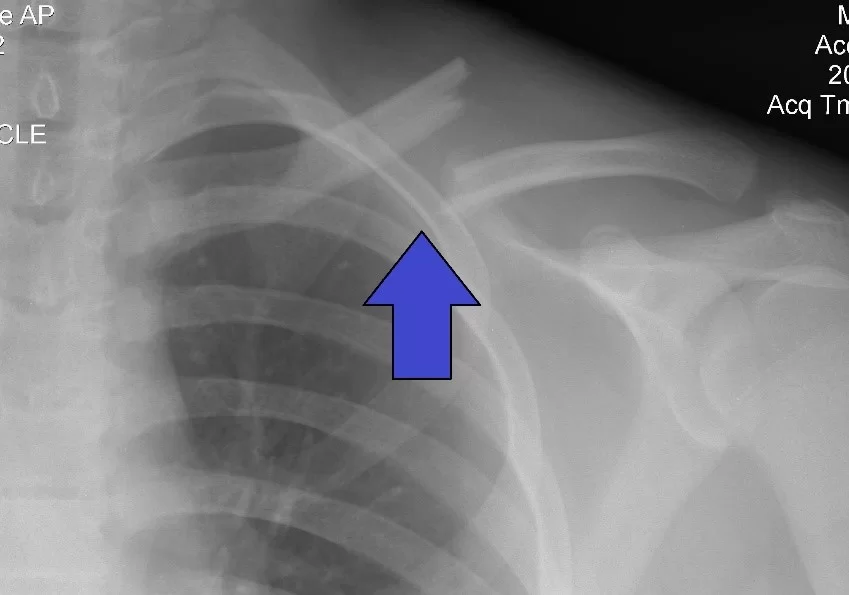

Xương đòn (xương quai xanh) là một xương có hình chữ S và có thể dễ dàng nhìn thấy ngay dưới da ở nhiều người.

Xương đòn có vai trò như một thanh chống để nối lồng ngực và đai vai.

Cơ chế gãy xương đòn: ngã té chống tay, té đập vai hoặc lực tác động trực tiếp vào vùng vai.